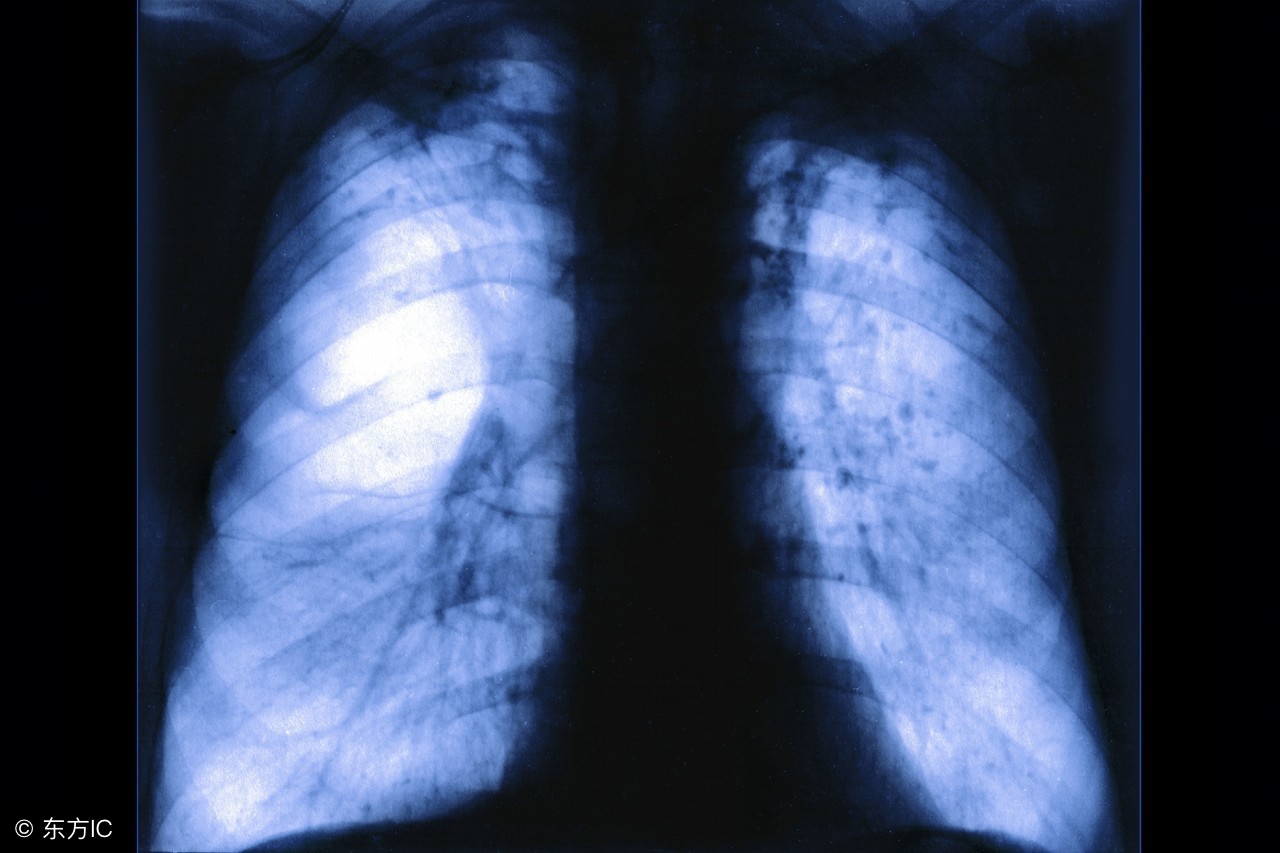

患上肺气肿的人可能会出现呼吸困难等情况,是比较棘手的一种疾病。那么患上肺气肿的话吃什么比较好呢?下面就来给大家讲讲肺气肿吃什么好,它们给你好身体哦!